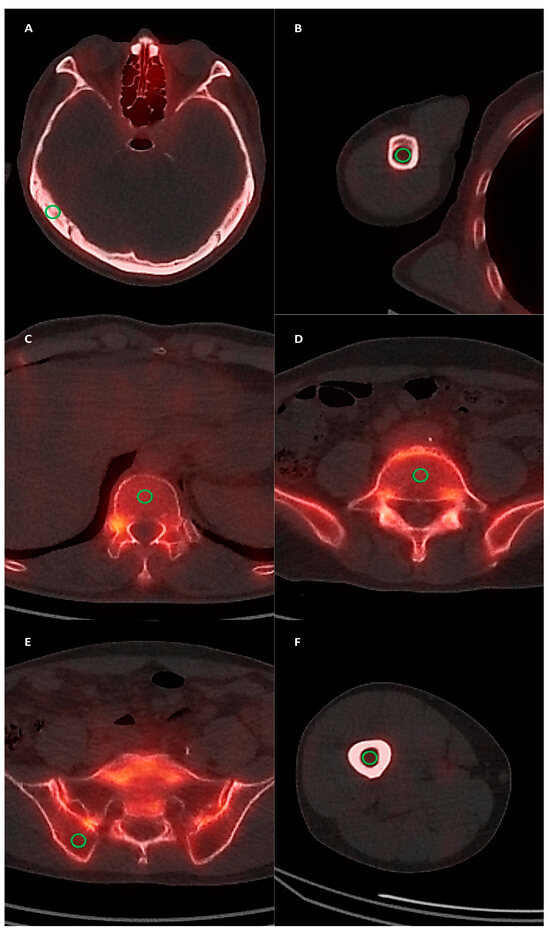

2.3. SPECT/CT Image Analysis

3.2. Normal Bone Uptake of SPECT/CT Images

3.3. Diagnostic Ability of SPECT/CT Imaging Parameters